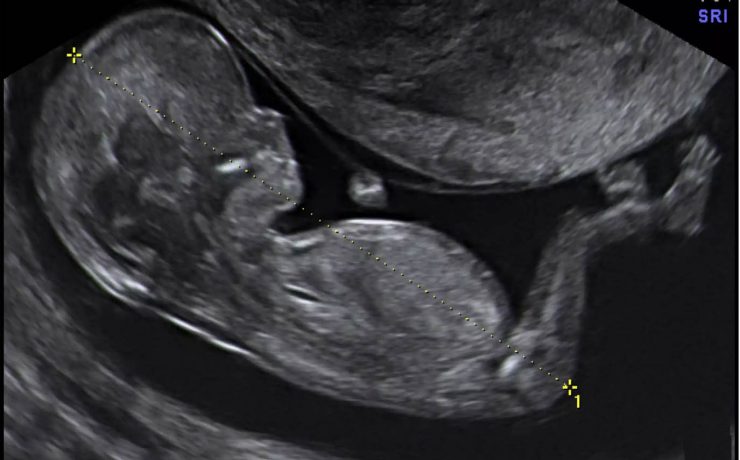

El signo del lirio caído , fue descrito hace más de 40 años en pielografía de eliminación y corresponde al aspecto que adquiere el sistema pieloureteral inferior en un riñón con doble sistema excretor, dado por una pelvis renal de orientación horizontal y cálices que se dirigen discretamente hacia cauda.